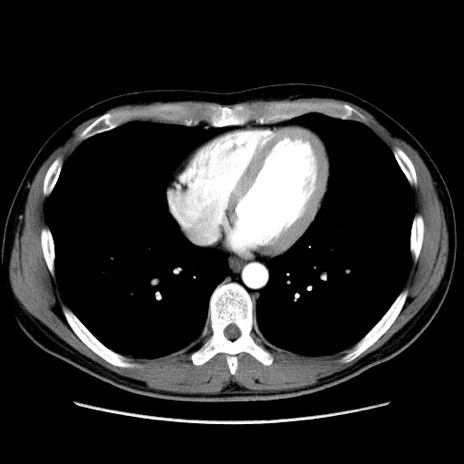

症例36(横断像)

【症例】20歳代 男性

【主訴】心窩部痛

【現病歴】今朝より上腹部痛あり。一旦軽快していたが再度出現したため救急要請。昨日夕に白身の魚を含む刺身を食べた。

【身体所見】BP 136/89mmHg、HR 74/min、BT 37.0℃、腹部:膨満、軟、心窩部に圧痛あり。反跳痛なし、筋性防御なし、腸雑音やや亢進あり。

【データ】WBC 17700、CRP 0.48